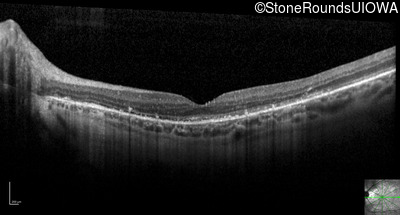

Optical Coherence Tomography - Right - 20/20 -2

Exemplar / OCT Stack